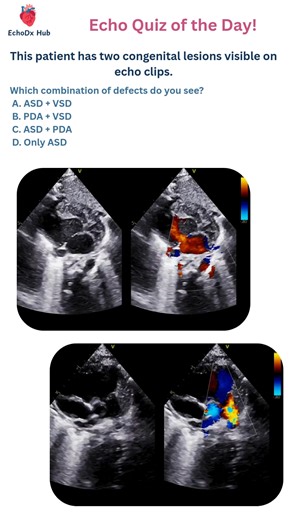

PDA Echo Findings 的热门建议 |

Echo Findings - PDA Echo

PDA - PDA

Views - PDA

2D Echo - PDA

PDA - 2D Echo

Echocardiography - PDA